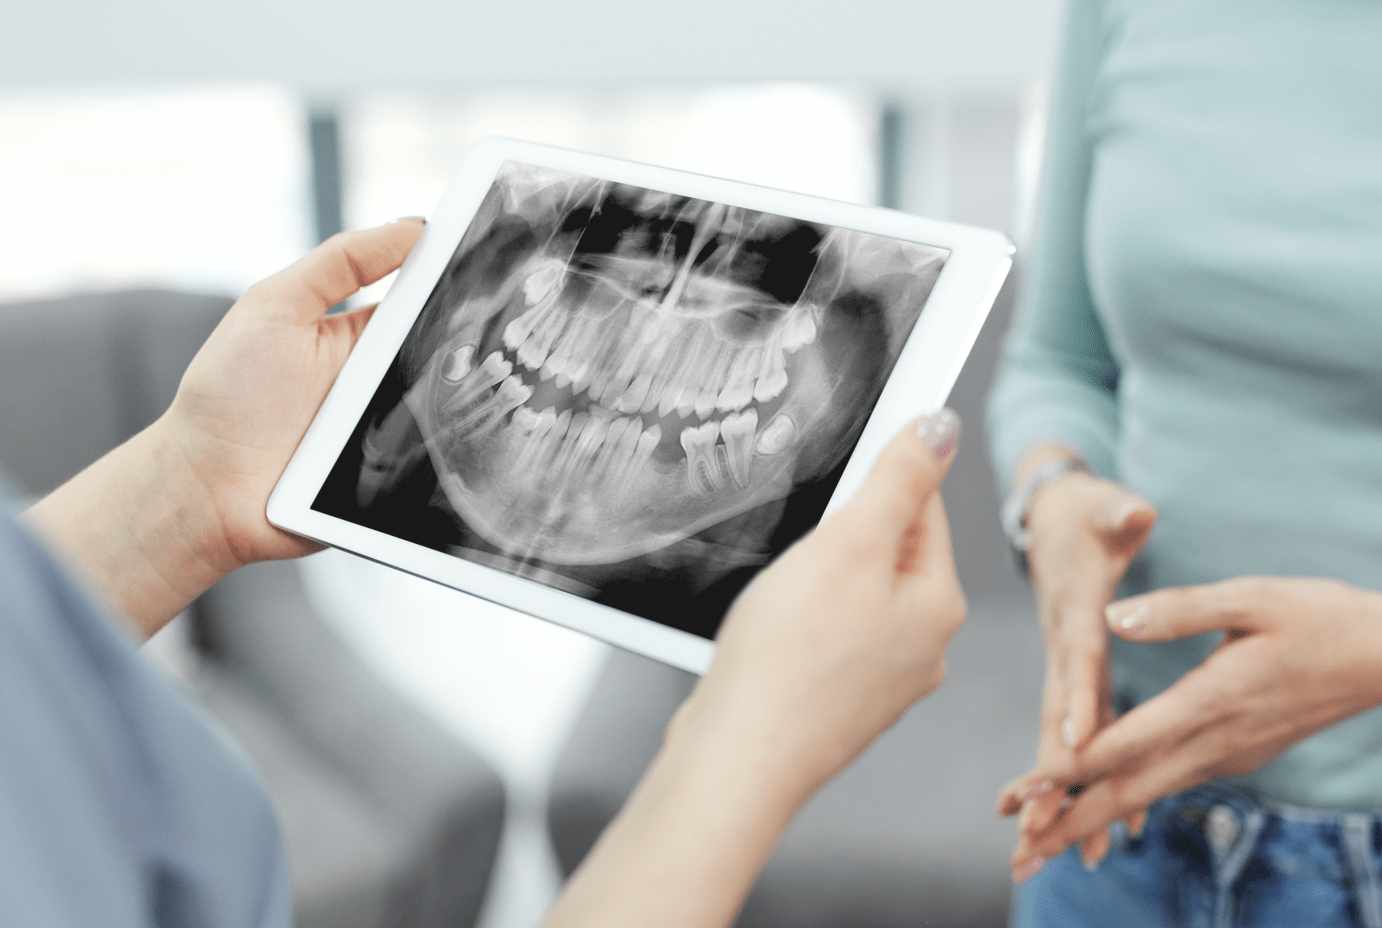

Ψηφιακή Ακτινογραφία

- Ο υψηλής τεχνολογίας ψηφιακός ακτινολογικός έλεγχος παρέχει μεγάλη προστασία τόσο στον ασθενή όσο και στο προσωπικό των ιατρείων μας. Ο ελάχιστος χρόνος έκθεσης κατά την ακτινογράφηση σημαίνει και πολύ χαμηλότερη ποσότητα ακτινοβολίας.

- Η απευθείας εμφάνιση της ακτινογραφίας στον υπολογιστή και η ανάλυση της μας δίνουν ένα υπερπολύτιμο διαγνωστικό εργαλείο ενώ εξοικονομούμε και πολύτιμο χρόνο για την περαιτέρω θεραπεία σας.